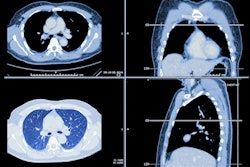

Dual-energy CT (DECT) is an effective tool for improving neuroimaging in the emergency room -- and making use of it can translate into a variety of benefits for patients, according to a recent presentation.

Dual-energy CT was introduced in 2006, and it can come in two forms, source-based or detector-based. Under the source-based DECT category are dual-source (two x-ray tubes), rapid tube voltage switching, split filter, and dual-spin devices, while detector-based CT may include dual-layer or photon-counting techniques. Over the years, the technology has shown promise for such indications as diagnosing hip prosthesis instability; gout workup; and assessing osteoporosis risk.

- Detection: "DECT identifies disease that may be otherwise invisible or challenging to see on conventional CT imaging," he said.

- Characterization: (for example, differentiating iodine staining from cerebral hemorrhage). "[The technique] provides additional information about material composition beyond traditional attenuation values, making it possible to further characterize findings without additional imaging," Sodickson said.

- Reductions in length of stay, imaging use, and radiation dose: "DECT can reduce the need for follow-up imaging, particularly when differentiating intracranial calcification from potential hemorrhage," he said. "This can reduce emergency department length of stay, downstream imaging use, and associated radiation exposure."